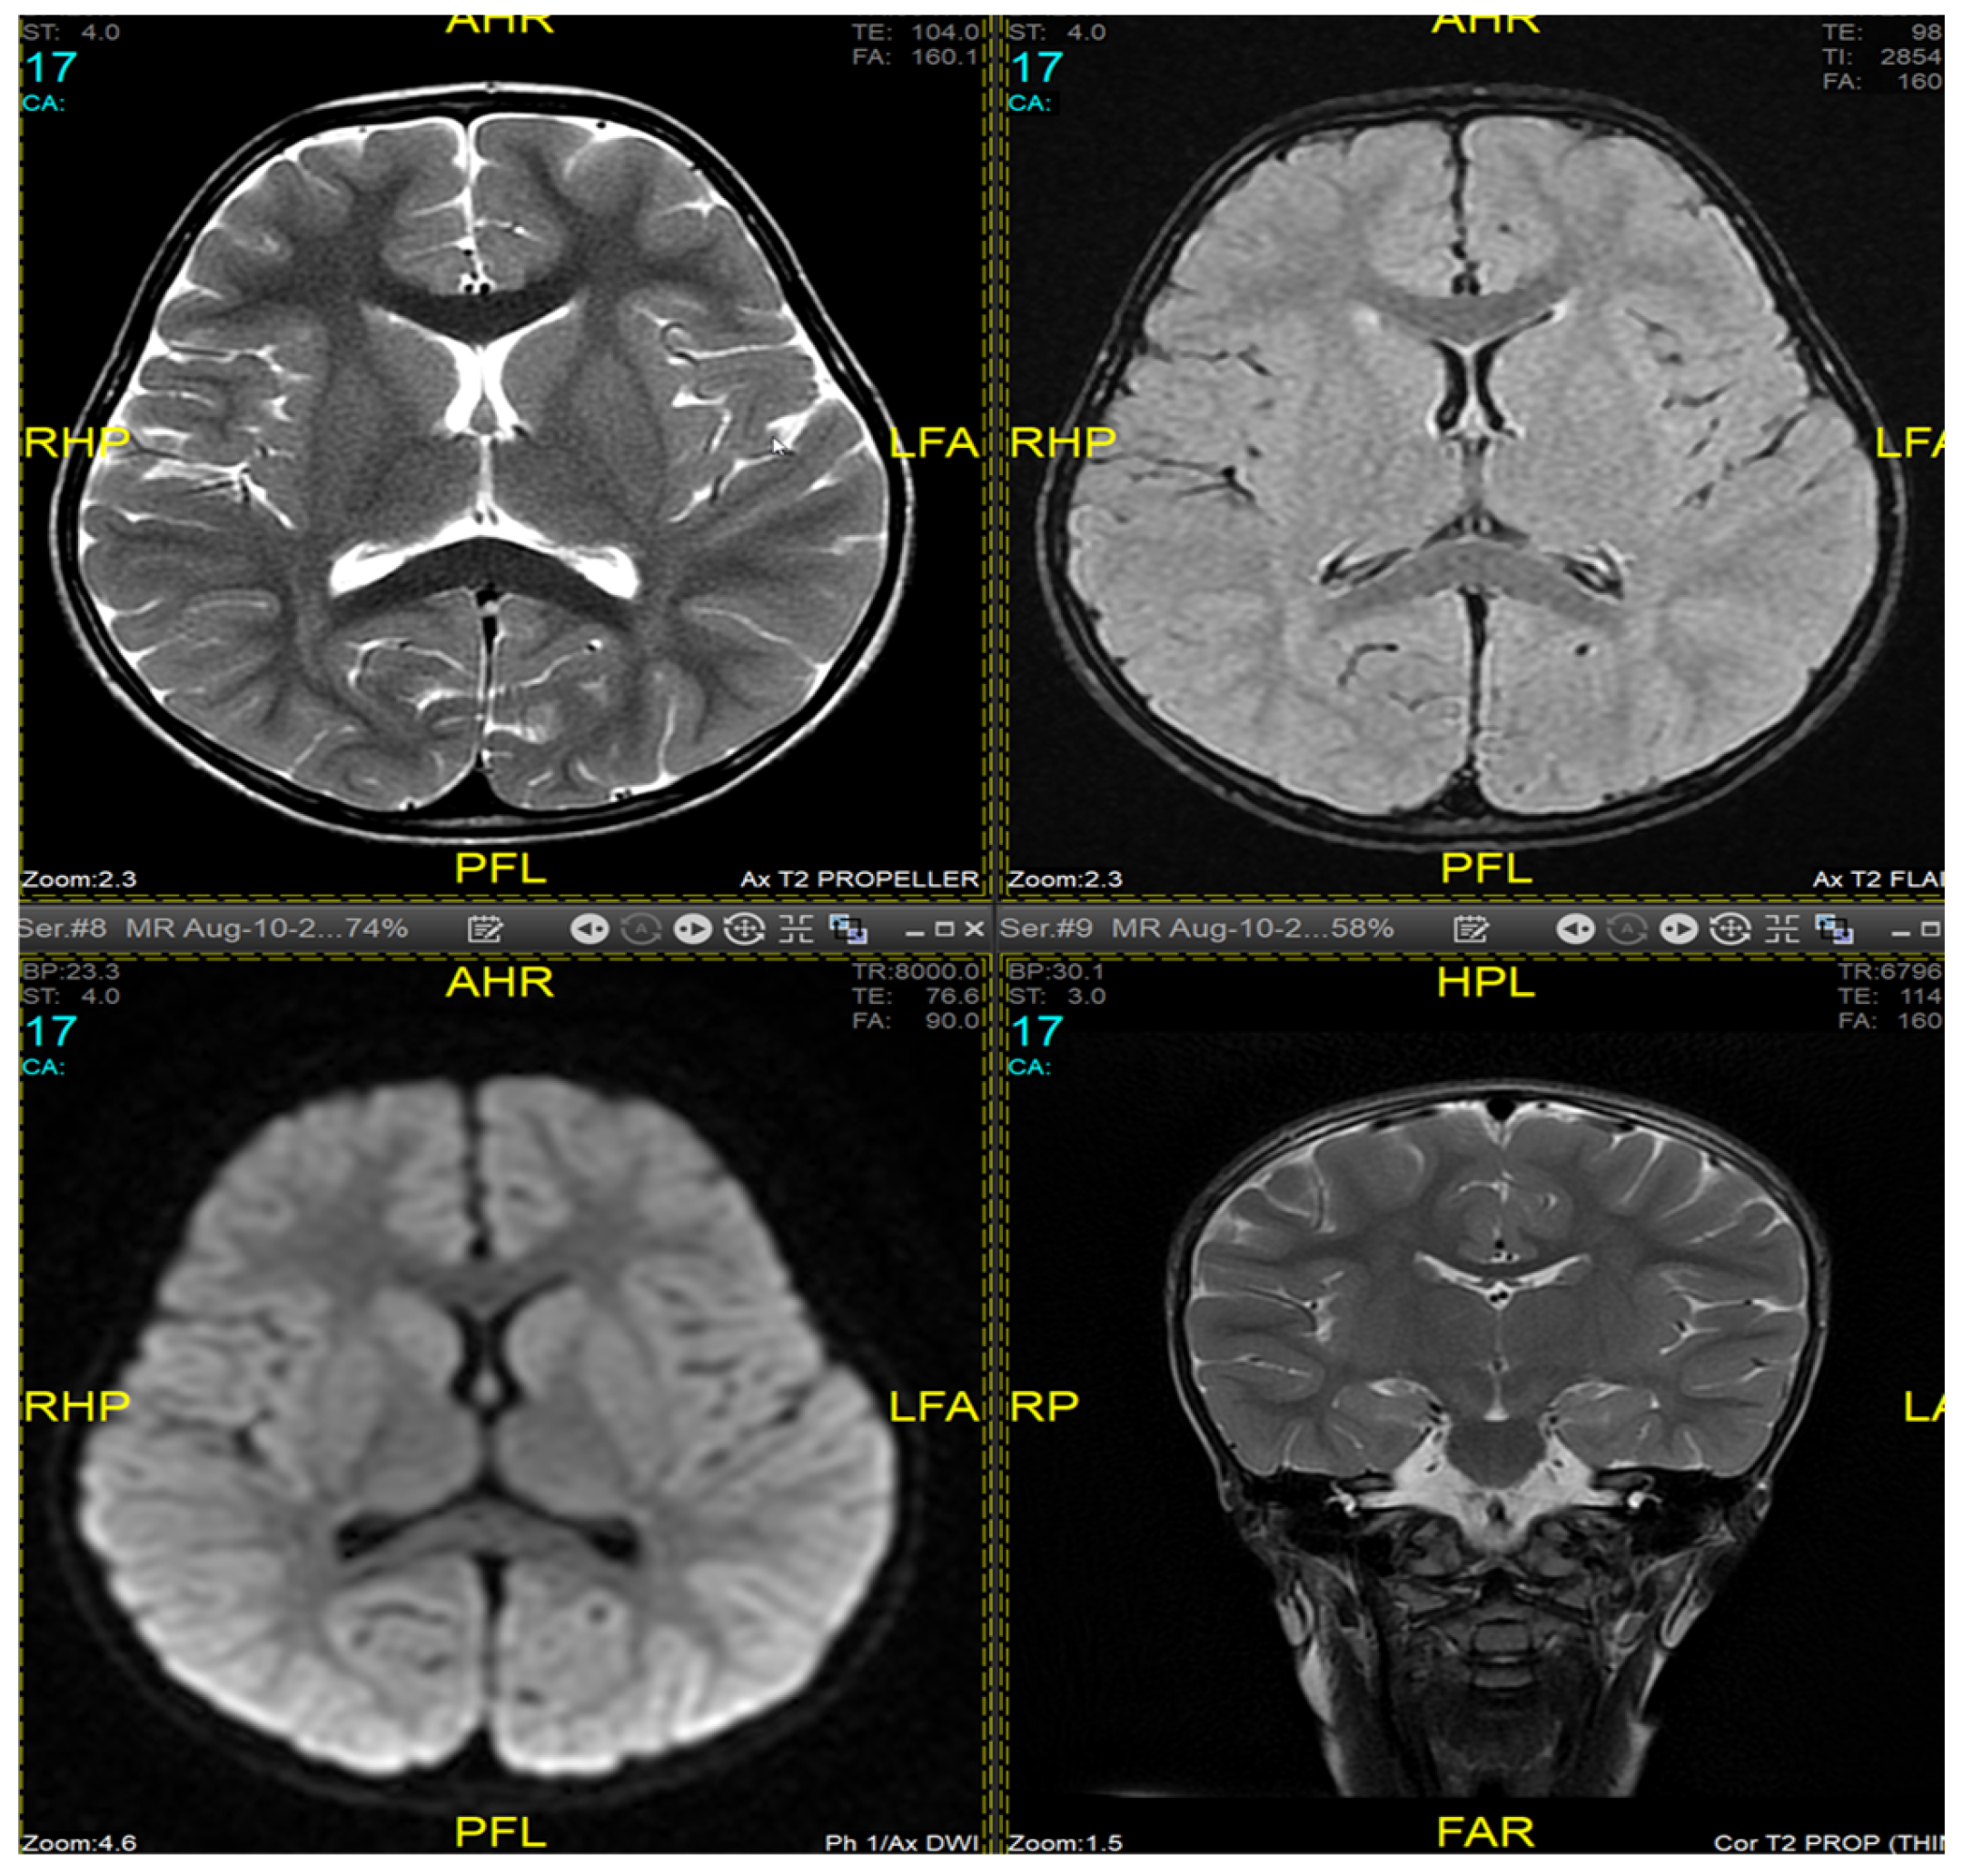

2. Case Presentation